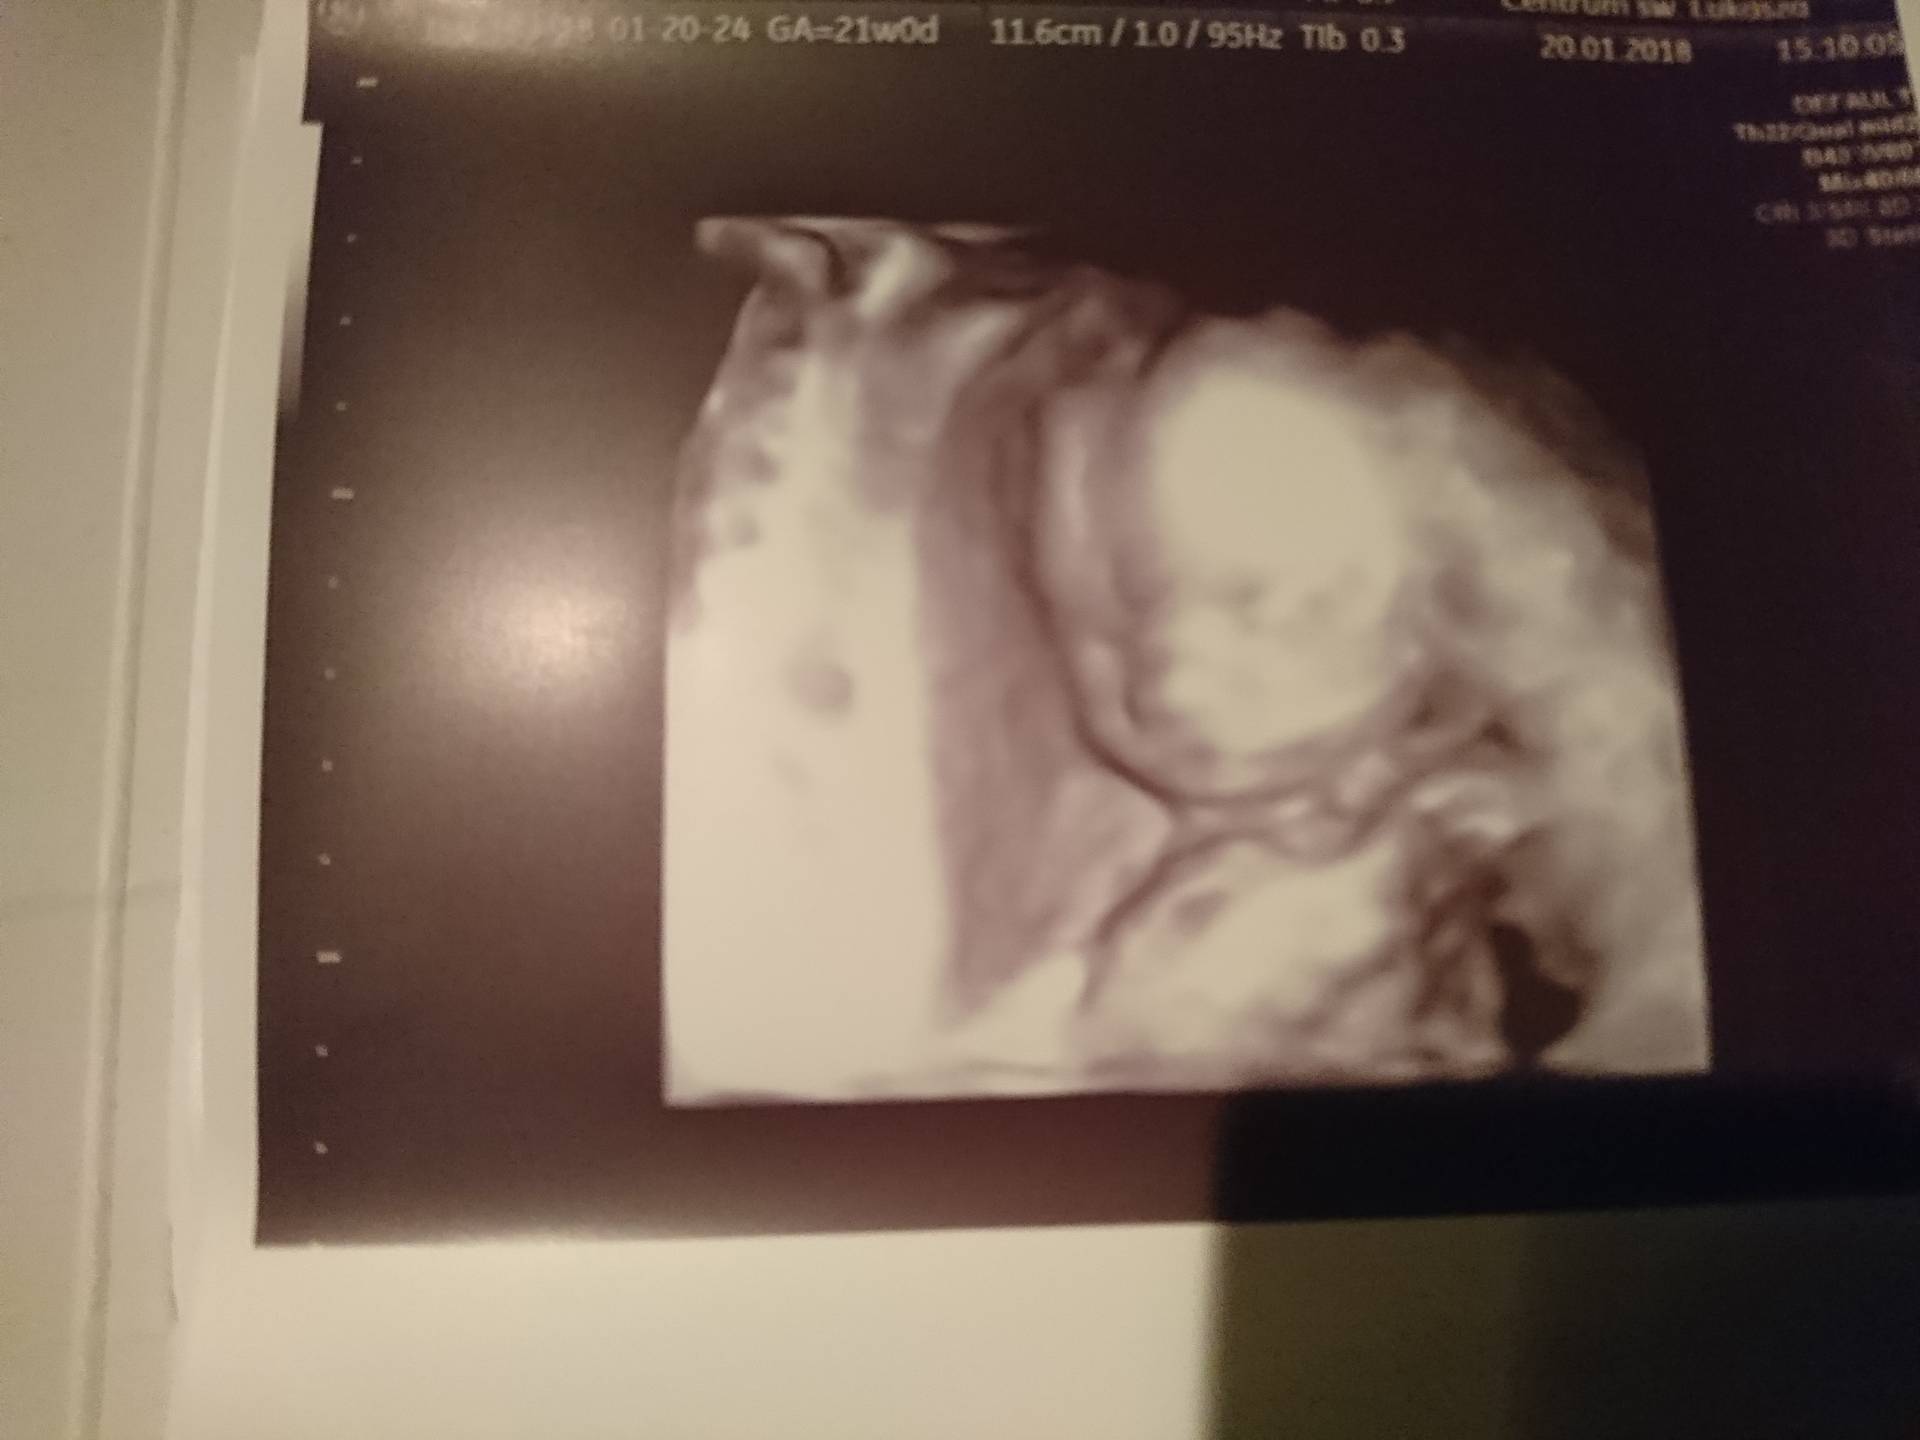

Co oczywiście najważniejsze dzidzia rozwija się prawidłowo, wszystko w porządku z serduszkiem itp. Waży 409 g

iiiiii na 80% jest dziewczynka

Pan doktor mówi że całe badanie ma złożone nóżki, ale ani na chwilę nic innego się tam nie pokazało